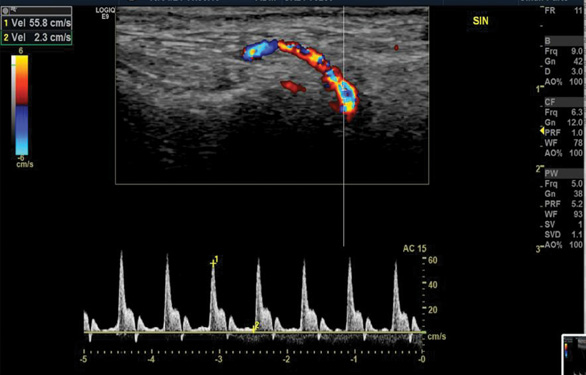

Five years later, at the follow-up visit, the patient did not feel any pain or discomfort in the temporal area bilaterally. No inflammatory signs of temporal arteries were detected (Fig. 3). The control color-coded duplex sonography showed no halo sign, and normal blood flow velocities were registered (Fig. 4). It was concluded that there were no clinical or ultrasound signs of temporal vasculitis.

Normal blood flow velocities of the right (A) and left (B) superficial temporal arteries were observed without the ‘halo’ sign.